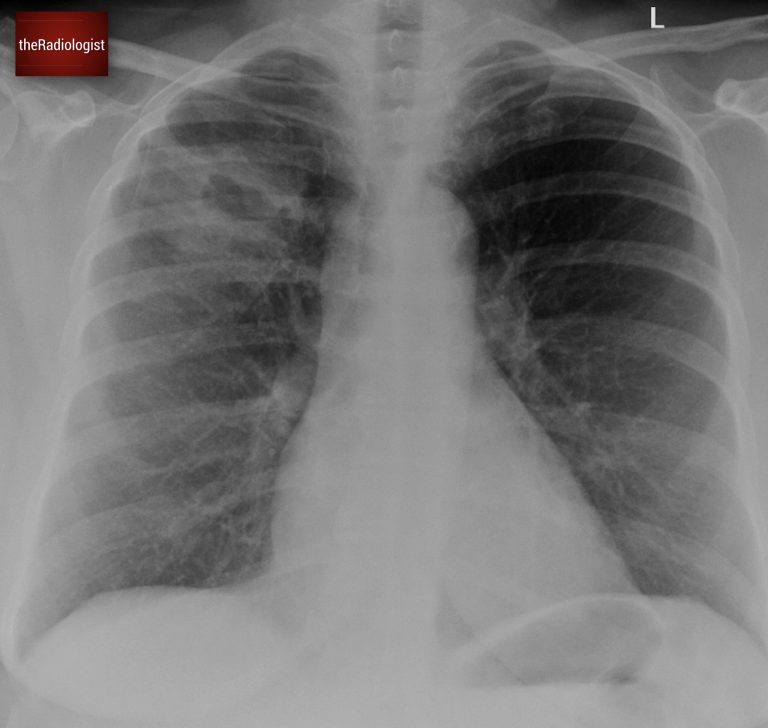

Case two introduction

A single cavitating lesion does not always mean lung cancer. In a separate case, a female patient in her 60s presented with a history of cough and fever, along with imaging that showed a cavitating lesion in the right lung. Have a look at the X-Ray below:

PA Chest X-Ray

The X-ray revealed a cavitating lesion surrounded by consolidation. How do we know this is consolidation? Look for air bronchograms: small, round lucencies within the opacity, a hallmark of consolidation.

There are air bronchograms surrounding the cavitating lesion suggesting the presence of consolidation.

Unlike the previous case, there was no rib destruction. However, there was increased density within the right paratracheal region and an enlarged azygos contour.

This points towards right sided paratracheal lymph node enlargement. Bulky lymph nodes can point more towards cancer however mild node enlargement can be seen in both infections and cancer.

Look at the right paratracheal region: we have loss of the right paratracheal stripe and there is increased density in this region suggesting nodal enlargement.